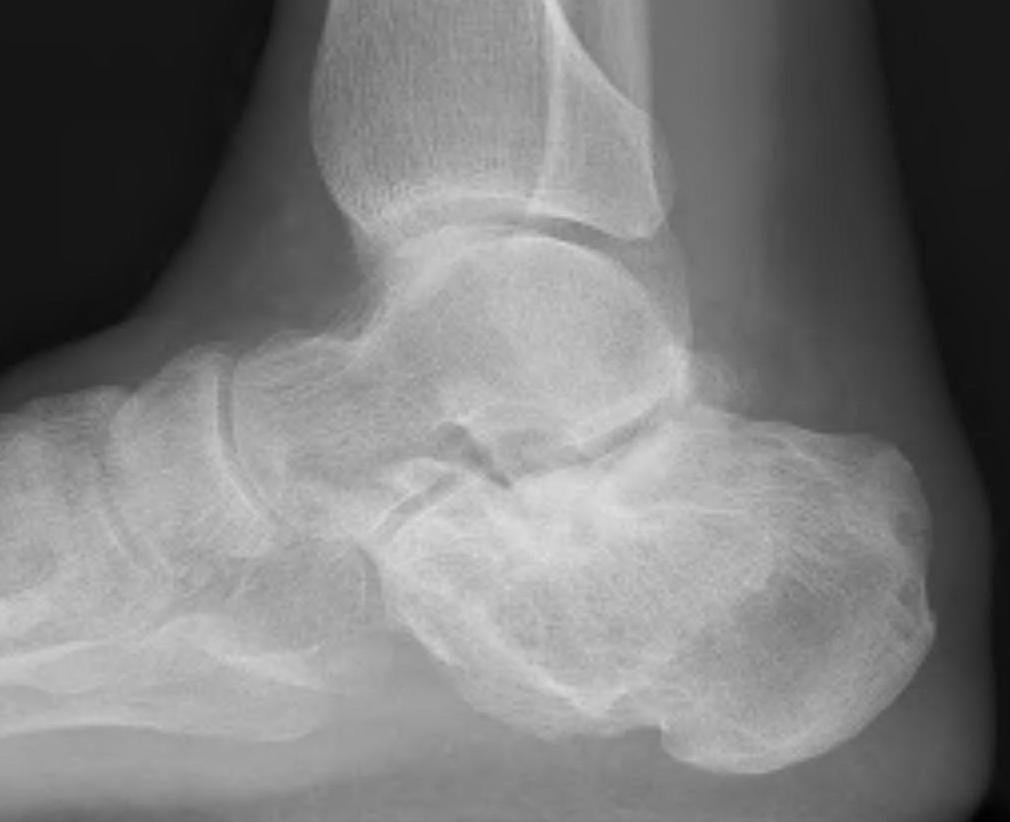

CT

Subluxation of TNJ with advanced STJ OA

TNJ OA with posterior / medial / anterior facet OA of the subtalar joint